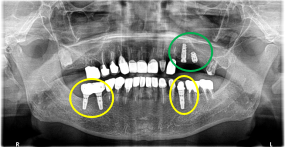

男性 Eさん 80代 (インプラント)

主訴

左上2本が動いていて、噛むと痛みがある。歯がないところに歯を入れたい。

治療内容

左上第二小臼歯と第一大臼歯の歯根が破折していたため、保存することができず抜歯しました。第一小臼歯は、すでにありませんでしたので、2本抜歯後3本欠損のところにインプラントを2本埋入しました。

所感

2006年10月に右下と左下の欠損部分にインプラント治療をしました。今回も左上の歯を失ったところは、インプラント治療を希望されました。

インプラント2本:¥363,000✕2本=¥726,000(税込)

ポンティック1本:¥115,500(税込)

合計:¥841,500(税込)

Before

※赤丸は、歯根が破折していたため抜歯しました

※黄色丸は、2006年10月に埋入したインプラント

After

※緑丸は、今回埋入したインプラント